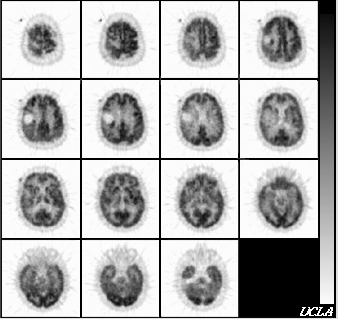

© 1994-2000 Crump Institute for Molecular Imaging

UCLA School of Medicine